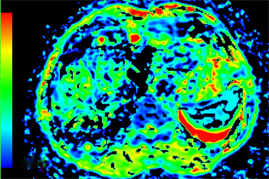

Figure 2. Axial MRI images of the same patient as in Figure 1 after TACE treatment. (a) T1-weighted unenhanced image shows a hypointensive lesion in right lobe of liver. (b) Arterial phase contrast-enhanced image shows the central necrotic area and peripheral enhanced area in the lesion. (c) ADC map. (d) Dslow map. (e) Dfast map. (f) f map.